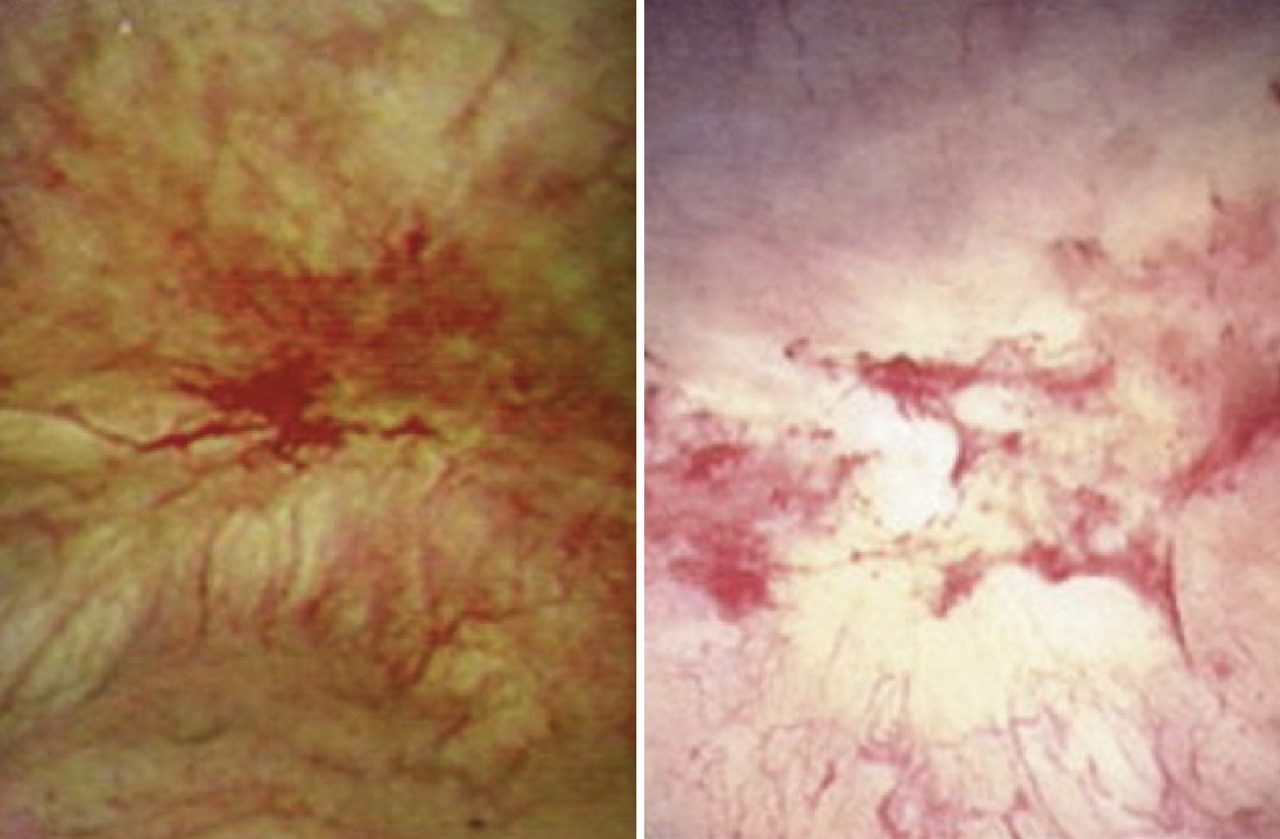

• dans une minorité de cas, des zones d’aspect inflammatoire d’une typologie très variable sont mises en évidence. Le plus souvent, ces lésions sont peu nombreuses et siègent exclusivement sur les parois mobiles de la vessie. Cependant, elles peuvent parfois être plus étendues : ce sont les ulcères dits de Hunner (fig. 1), décrits en 1915, à une époque où le matériel endoscopique n’était pas ­développé comme aujourd’hui (lumière blanche, caméra etc.). Il est très important de diag­nostiquer ces ulcères ; plusieurs auteurs s’accordent pour penser qu’en leur présence, il ne s’agit pas d’un SDV/CI, et la prise en charge des ­patients diffère.6

Le deuxième temps de l’examen endo­scopique vésical consiste en la réalisation d’une hydrodistension de la vessie jusqu’à une pression de 80 cm d’eau pendant une durée non consensuelle de quelques minutes (3 minutes en moyenne). La vessie est ensuite vidée, et un nouvel examen visuel est réalisé. ­Celui-ci met le plus ­souvent en évidence des points de saignement plus ou moins nombreux, diffus ou hémorragiques appelés pétéchies ou glomérulations (fig. 2).

Dans de rares cas, des lésions inflammatoires peuvent devenir visibles alors qu’elles ne l’étaient pas lors de l’examen initial des parois ; ces lésions, si elles sont visibles dès la première exploration, s’étendent souvent après l’hydro­distension. Elles peuvent rester isolées ou, plus souvent, être accompagnées de pétéchies diffuses. L’interprétation diagnostique de ces situations distinctes n’est pas établie.